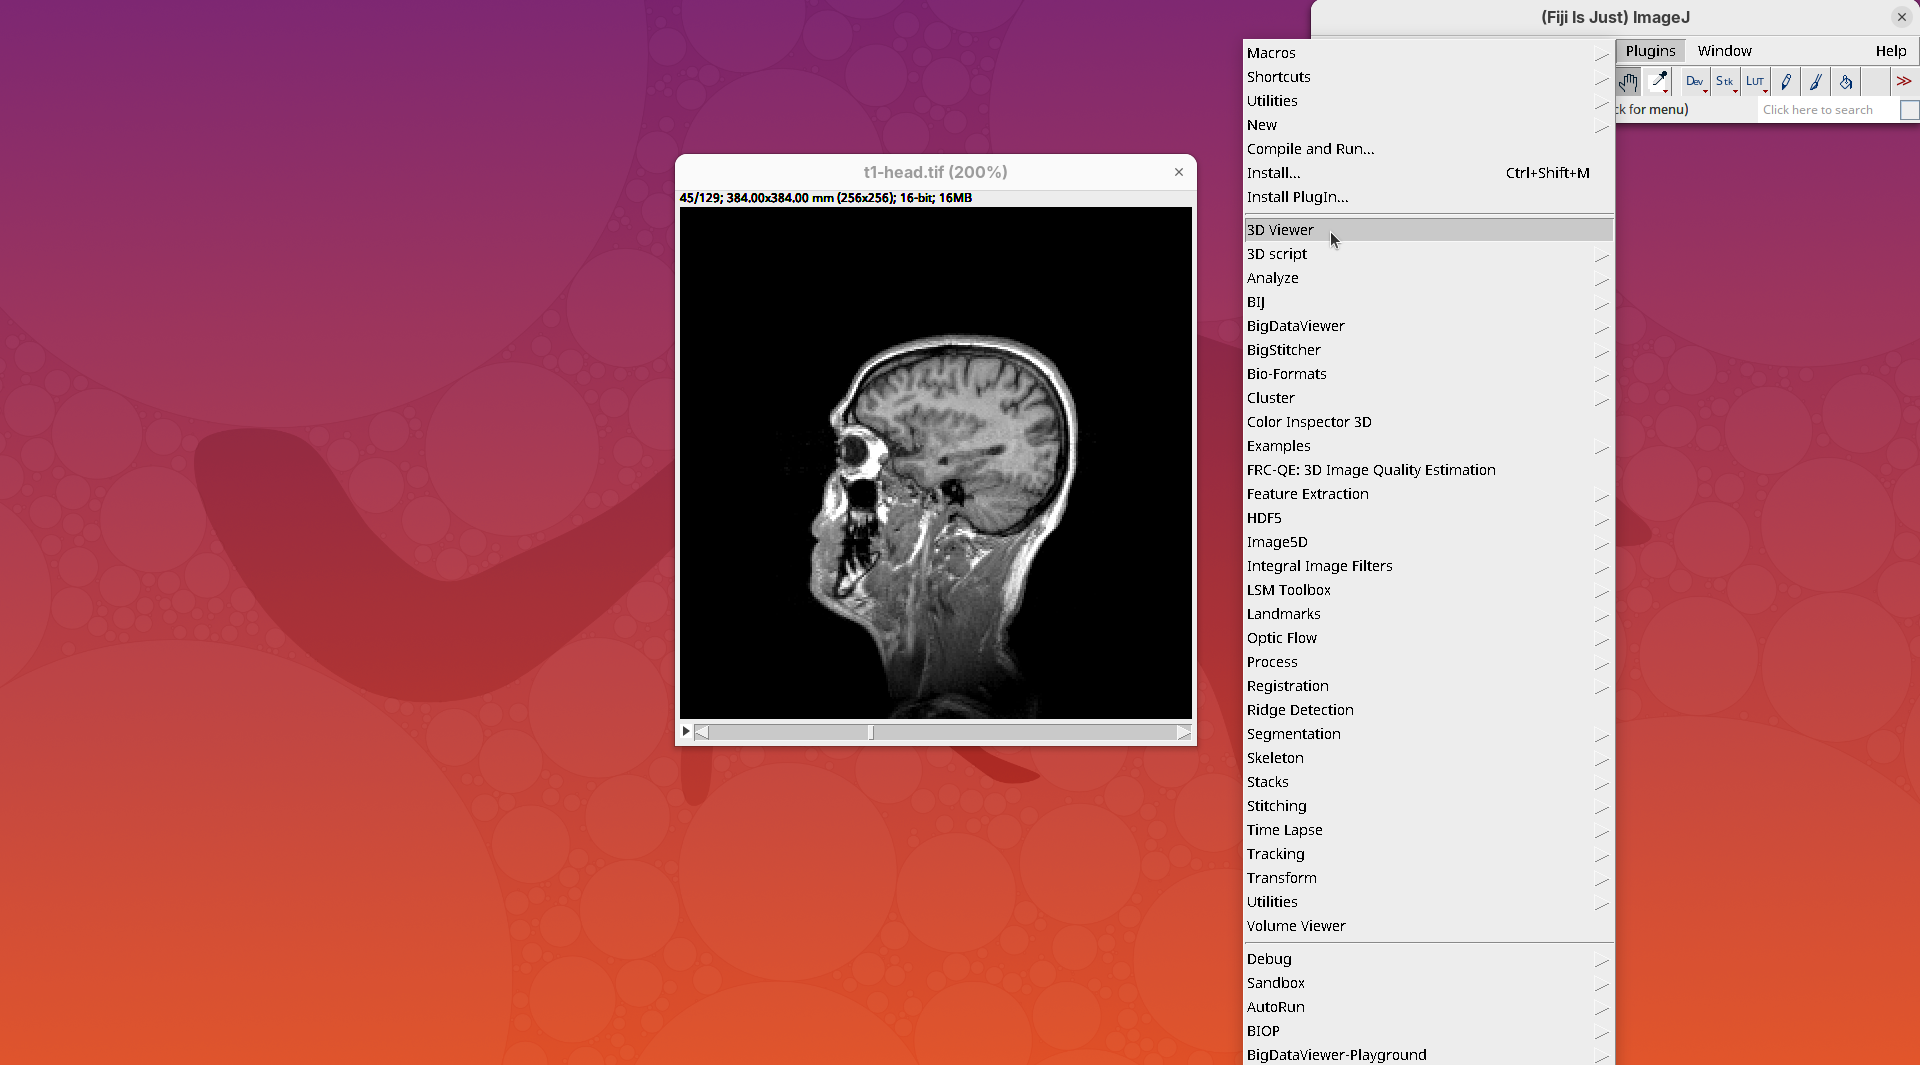

3D Viewer

The 3D Viewer (Schmid et al. 2010) is a 3D visualization plugin bundled in Fiji. It has been the default 3D rendering engine for many years and provides a good starting point for visualizing and interacting with 3D images. The interface provides some rendering and animation options, but it is possible to create more advanced visualizations and animations with code. For more details, please consult the documentation.

Here, we’ll only open our dataset with 3D Viewer for visualization.

- Go to

Plugins>3D Viewer.

An import dialog will open. In addition to the image field itself, pay attention to the Resampling factor parameter. The default is 2, which means 2x downsampling of the original stack. Always downsample at least 2x because 3D Viewer will crash when trying to open large datasets.

- Click

OKon the options dialog and when asked about converting to 8-bit.

The main interface will open.

- Explore the sample interactively.